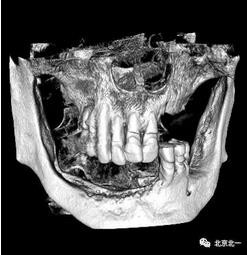

圖一至圖六明顯看出右側(cè)頦孔位于牙槽嵴頂。很清晰看出頦孔區(qū)的U型形狀。

圖七:采用A04技術(shù),拔除下頜余留牙,修整骨平面。在頦孔前方傾斜植入兩枚植體,避開(kāi)頦孔。減少懸臂。前牙區(qū)植入兩枚直的植體。完成即刻修復(fù)。一日得牙,缺牙后多少年來(lái)都沒(méi)有吃過(guò)蘋果的滋味,到種植牙時(shí)代,想吃什么就吃什么, 我的健康我做主。